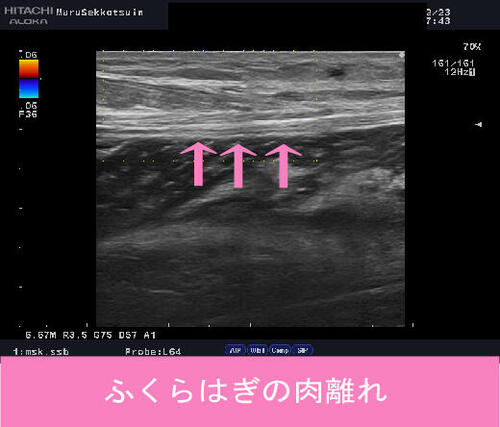

いつも通りしっかり問診、視診、触診後、確認のためエコー検査。

結果「腓腹筋内側頭部末梢付着部の肉ばなれ」と判明。

この腓腹筋内側頭部末梢付着部は、

力学的に筋肉からアキレス腱に移行する場所であり弱く、

中高年の肉ばなれは、ほとんどこの場所に発生します。